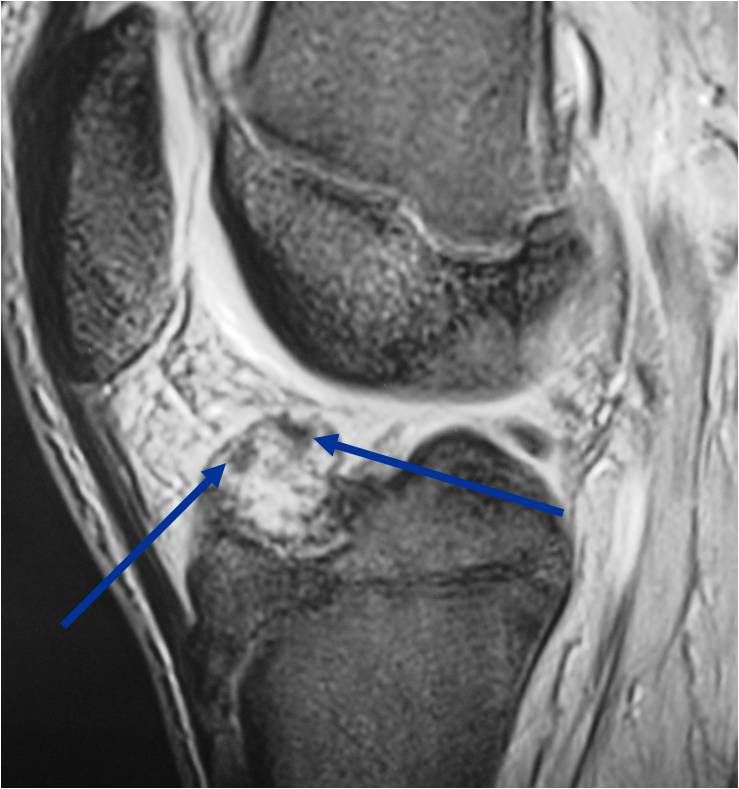

MRI appearance:

- Geographic, well circumscribed lesion in the epiphysis

- Intermediate Signal on T1

- High signal on T2 mixed with low signal areas (low signal areas proposed to be secondary to lysosomal content of highly cellular areas)

- Fluid/Fluid levels demonstrated in tumors that have undergone ABC change (aneurysmal bone cyst change)

- Extensive Surrounding edema is common

- Joint effusion in 30-50% of cases